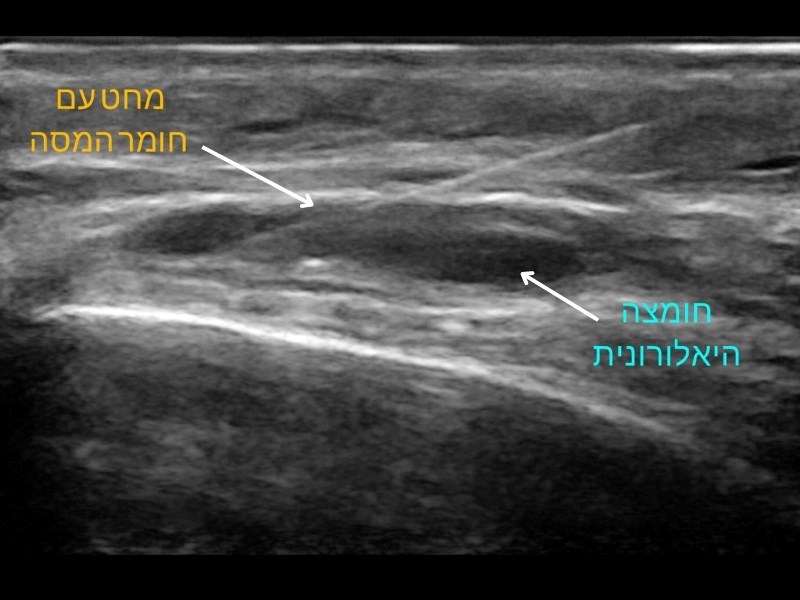

המסת חומצה היאלרונית. צילום: פרטי

בדומה להזרקת חומצה היאלרונית מכוונת אולטרסאונד, גם במקרה הזה האולטרסאונד הופך את פעולת ההמסה לבטוחה ולמדויקת הרבה יותר. ראשית, באבחון ניתן לראות האם יש חומצה היאלורונית ברקמה והאם ההמסה נדרשת. במידה שניתן להדגים חומצה היאלרונית באזור המיועד, אפשר לבצע את ההמסה תחת אולטרסאונד בזמן אמת ולהזריק את ההיאלרונידאז כשהמחט נמצאת בדיוק במקום הרצוי - להשגת אפקט מירבי גם בהזרקת כמויות קטנות יחסית ובכך לצמצם את התפשטות ההיאלרונידאז לאזורים סמוכים.

לסיכום, שימוש באולטרסאונד לפני המסת חומצה היאלרונית יכול לחסוך את הצורך בהמסה במידה שלא נצפית חומצה היאלרונית וכאשר יש צורך בהמסה - המסה מוכוונת אולטרסאונד היא אפקטיבית יותר, בעיקר במקרים שבהם הזרקת החומצה המקורית התרחשה לאזור עמוק, שלא ניתן להרגישו בקלות סמוך לפני העור.